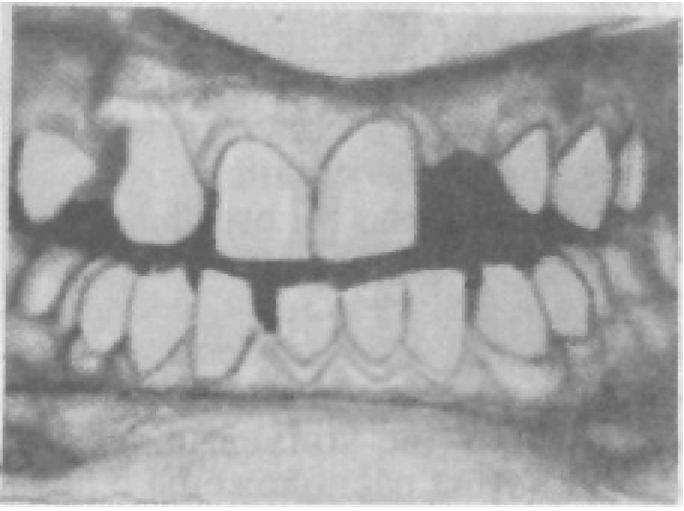

Смещение зуба в любом направлении — симптом заболевания зубочелюстной системы. Выявление этого симптома требует от врача проведения дополнительных методов исследования, установления механизмов смещения, а по результатам всего комплекса диагностического процесса — установления диагноза. Так, вестибулярное смещение центральных резцов с образованием между ними промежутка (ложная диастема); смещение передней группы зубов, супраокклюзионное положение одного из резцов с различной степенью ротации патогномонично для ряда заболеваний — пародонтоза, пародонтита (рис. 21).

Доказательством смещения передней группы зубов является нахождение режущих краев резцов, а иногда и клыков верхней челюсти ниже красной каймы губы. Значительное их обнажение при разговоре свидетельствует об их перемещении вертикально или вестибулярно за счет протекающих в пародонте патологических процессов. Смещение зубов вестибулярно, как правило, сопровождается образованием диастемы и трем, а сами зубы как бы отодвигают губу кверху. Это смещение может вести к образованию открытого прикуса или обусловить перемещение нижних резцов вверх.